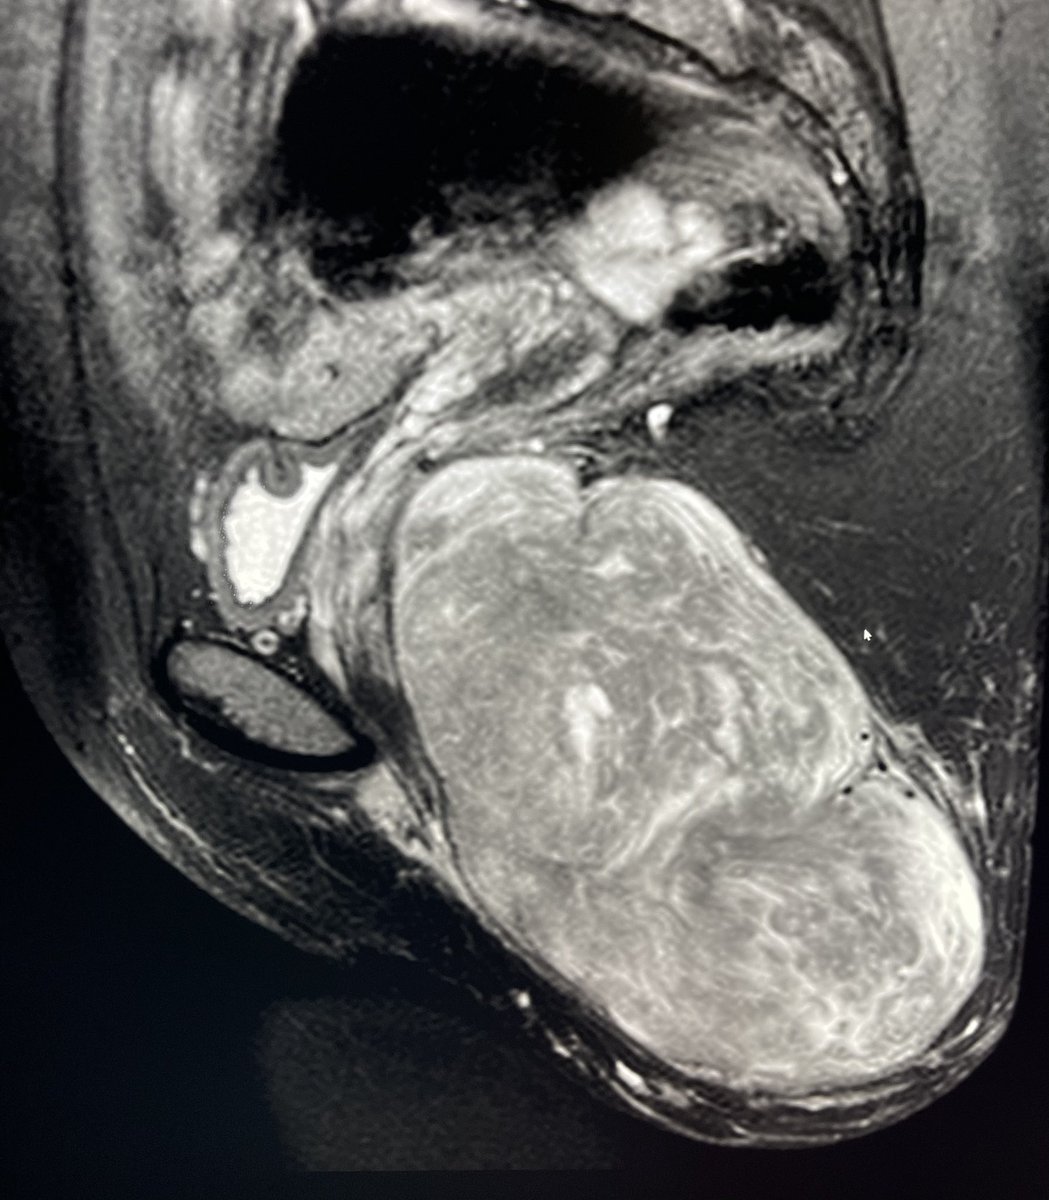

Pelvic floor leiomyosarcoma, treated @UTHouston_IR by bland #embolization prior to #excision to minimize intra and postoperative blood loss. Very selective embolization of the tumor while maintaining perfusion to the remaining pelvic organs and structures.